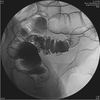

9

ERCP with stone in common bile duct